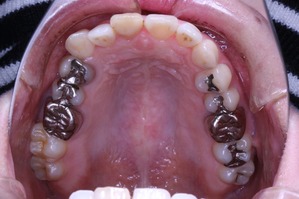

虫歯治療はきちんとされてますが、奥歯に全部銀歯の状態の歯があります。

当然、神経もない歯です。治療されたのはだいぶ前とのことでした。

しかしながら、いつ治療したか記憶にない銀歯があります。神経もとってしまってますし、中がどのような状態になっているか把握できません。治療中に歯がとれてしまい、結果的に抜歯となってしまう可能性もございます。

上の歯列はどうでしょうか?